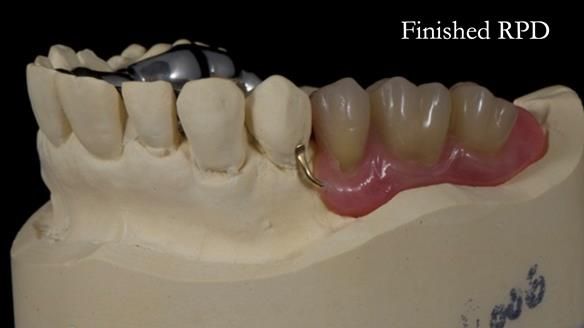

Welcome to Newsletter 64. I'll walk you through the process of providing a Mk 2 metal-based partial denture (RPD), for Ian a retired Veterinary Surgeon aged 78. The RPD was made at an increased vertical dimension and acted as an occlusal stabilisation splint - reducing the wear and bite force on the remaining natural teeth.